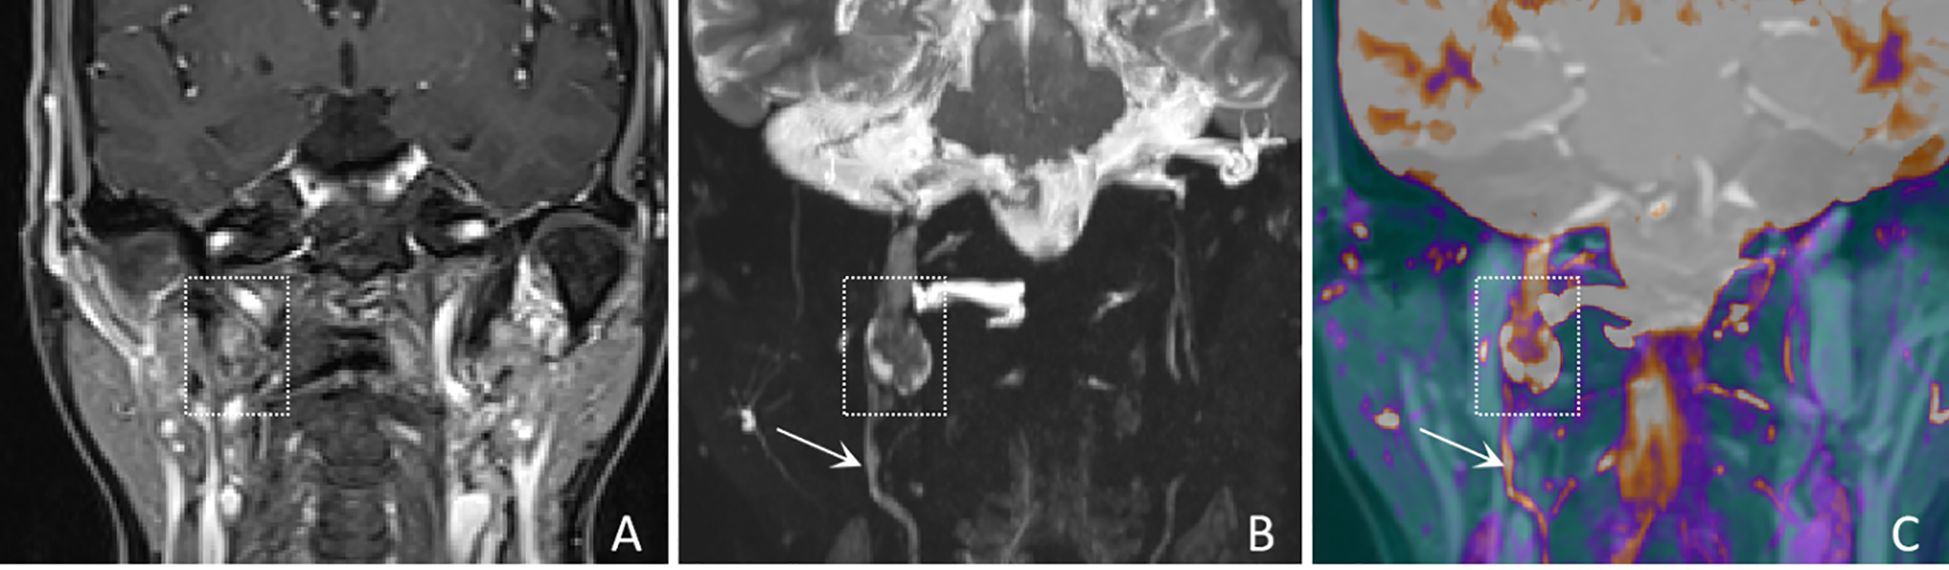

In terms of nerve involvement pattern, the neurogenic group predominantly exhibited focal involvement (92.9%), while the non-neurogenic group predominantly exhibited diffuse involvement (52.9%), with a statistically significant difference (p=0.002). Classical MRI findings showed a significantly higher incidence of the “dumbbell sign” in the neurogenic group compared to the non-neurogenic group (78.6% vs. 11.8%, p < 0.001). The “effacement of the fat plane” was exclusively observed in the non-neurogenic group, albeit with a relatively lower incidence (29.4%) (p < 0.001)(Table 3). Among the novel CE-MRN signs, the “enhanced target sign” (p=0.032) and “nerve tail sign” (p=0.018) were more common in the neurogenic group (Figure 2). Conversely, the incidence of the “nerve effacing sign” was more frequently observed in the non-neurogenic group (76.5% vs. 35.7%, p=0.033), which may indicate a malignant trend (Figure 3). No significant differences were noted between the neurogenic and non-neurogenic groups regarding enhancement patterns, nerve signal and morphology (Table 4).

Figure 2

MRI images showing coronal views of a human head. Panel A displays a standard MRI scan with focus on the central area. Panel B highlights a specific artery with a boxed region and arrow. Panel C presents a color-enhanced version, with similar focus areas marked for comparison.

Figure 2. A 61-years-old female with a schwannoma of the right glossopharyngeal nerve, showing “enhanced target sign” and “nerve tail sign”. (A) A coronal CE-T1WI image shows a nodule inferior to the right jugular foramen, exhibiting heterogeneous enhancement (white dashed boxes), with complete obscuration of the nerve. (B) A coronal CE-MRN image shows a central low signal intensity and peripheral high signal intensity, referred to as the “enhancement target sign” (white dashed box) and “nerve tail sign” (white arrow marked). (C) A coronal fused image more clearly shows the lesion (white dashed box) and the involved nerve (white arrow).

This study reveals that nerves are mainly affected focally in neurogenic tumors, whereas affected diffusely in the non-neurogenic malignancies. observation aligns with the localized expansive growth characteristics of benign neurogenic tumors such as schwannomas, and also reflects the pathological characteristics of malignant tumors spreading along the perineural spaces (1719). In the novel CE-MRN signs (14), the “Enhanced target sign” manifests as a central region of low signal intensity surrounded by a peripheral region of high signal intensity. The underlying formation mechanism may be related to the differential enhancement between the Antoni A zone (cell-dense zone) and the Antoni B zone (mucous-like matrix zone) in schwannomas (20). The “nerve tail sign” serves as a direct imaging marker for neurogenic tumors by directly demonstrates the anatomical continuity between the tumor and the host nerve (21). Additionally, the “nerve effacing sign” may serve as an indicator of malignant tumors with PNS. The solid components of the tumor, characterized by their abundant blood vascularity and contrast agent penetration, exhibit a diffuse signal reduction on CE-MRN. This imaging finding mimics the appearance of affected nerves being incorporated into the tumor mass (22). The novel series of signs offers a new perspective for assessing nerve involvement and tumor features.